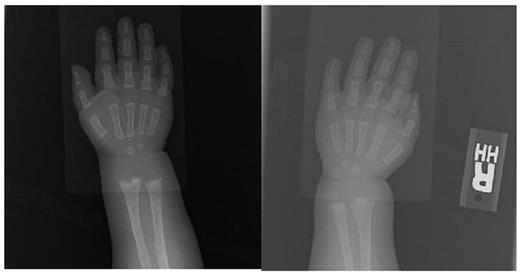

Case: Though subtly symptomatic from birth, our patient was diagnosed with CAT syndrome at four months of age after an episode of grossly bloody stools. After failed therapy with corticosteroids and vincristine, the patient was given bevacizumab 10mg/kg/dose every two weeks for four doses with excellent clinical response. After her fourth dose, a chest radiograph revealed incidental, asymptomatic metaphyseal lesions of the humeri. A complete bone survey revealed similar lesions in the metaphyses of nearly all of her long bones. (Figure 1) Given preclinical data suggesting these lesions could result from the use of VEGF inhibitors, bevacizumab was discontinued. All metaphyseal lesions subsequently resolved. (Figure 2) To our knowledge, this is the first report of bony toxicity in a human receiving bevacizumab. A thorough literature review on VEGF inhibitors revealed no reported cases of metaphyseal lesions or stunted growth in humans receiving VEGF inhibitors. Animal studies, however, suggest this may be possible. Growth plates consist of avascular cartilage that is eventually replaced by bone. This process requires invasion of the cartilage with metaphyseal blood vessels and has been shown to be directed by a VEGF gradient (